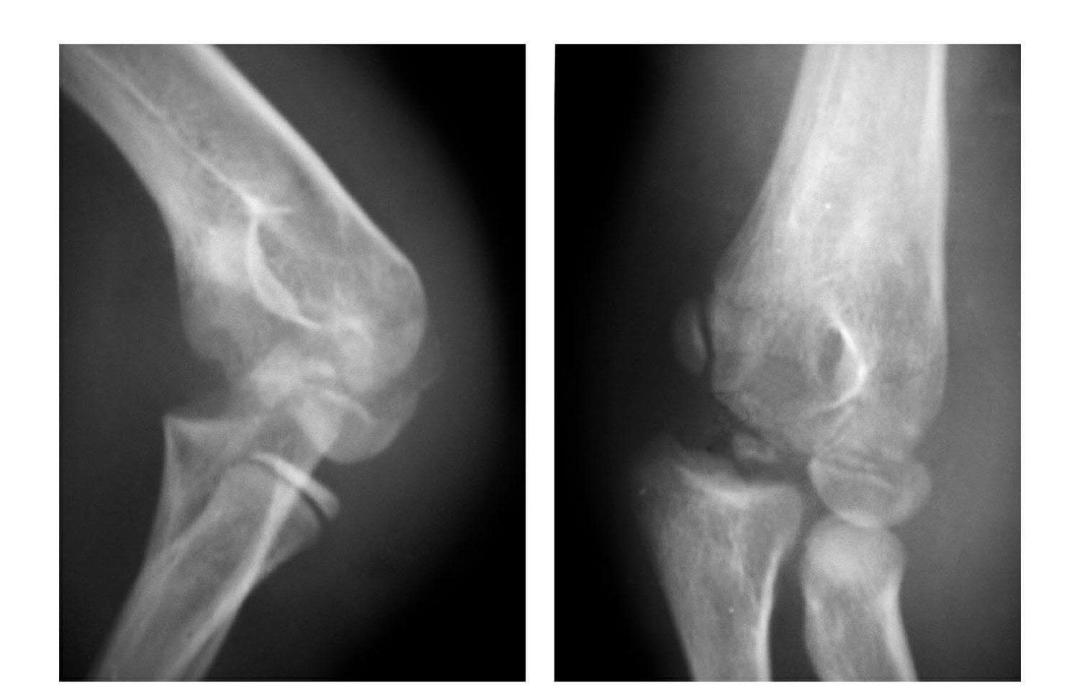

肘关节后脱位

例1:肘关节过伸性半脱位。

例2:肘关节过伸性半脱位并肱骨小头外缘骨折。

例3:肘关节后侧脱位。

例4:肘关节后外侧脱位。

例5:肘关节后内侧脱位合并滑车后缘骨折。

例6:肘关节后外侧脱位合并外髁劈裂骨折。

例7:肘关节后外侧脱位并桡骨头劈裂骨折,致肱骨小头将桡骨头骨块推向肘关节内前侧。

例8:肘关节后侧脱位并桡骨头外侧关节面骨折与尺骨冠状突骨折,致该骨块移向肘关节内下方。